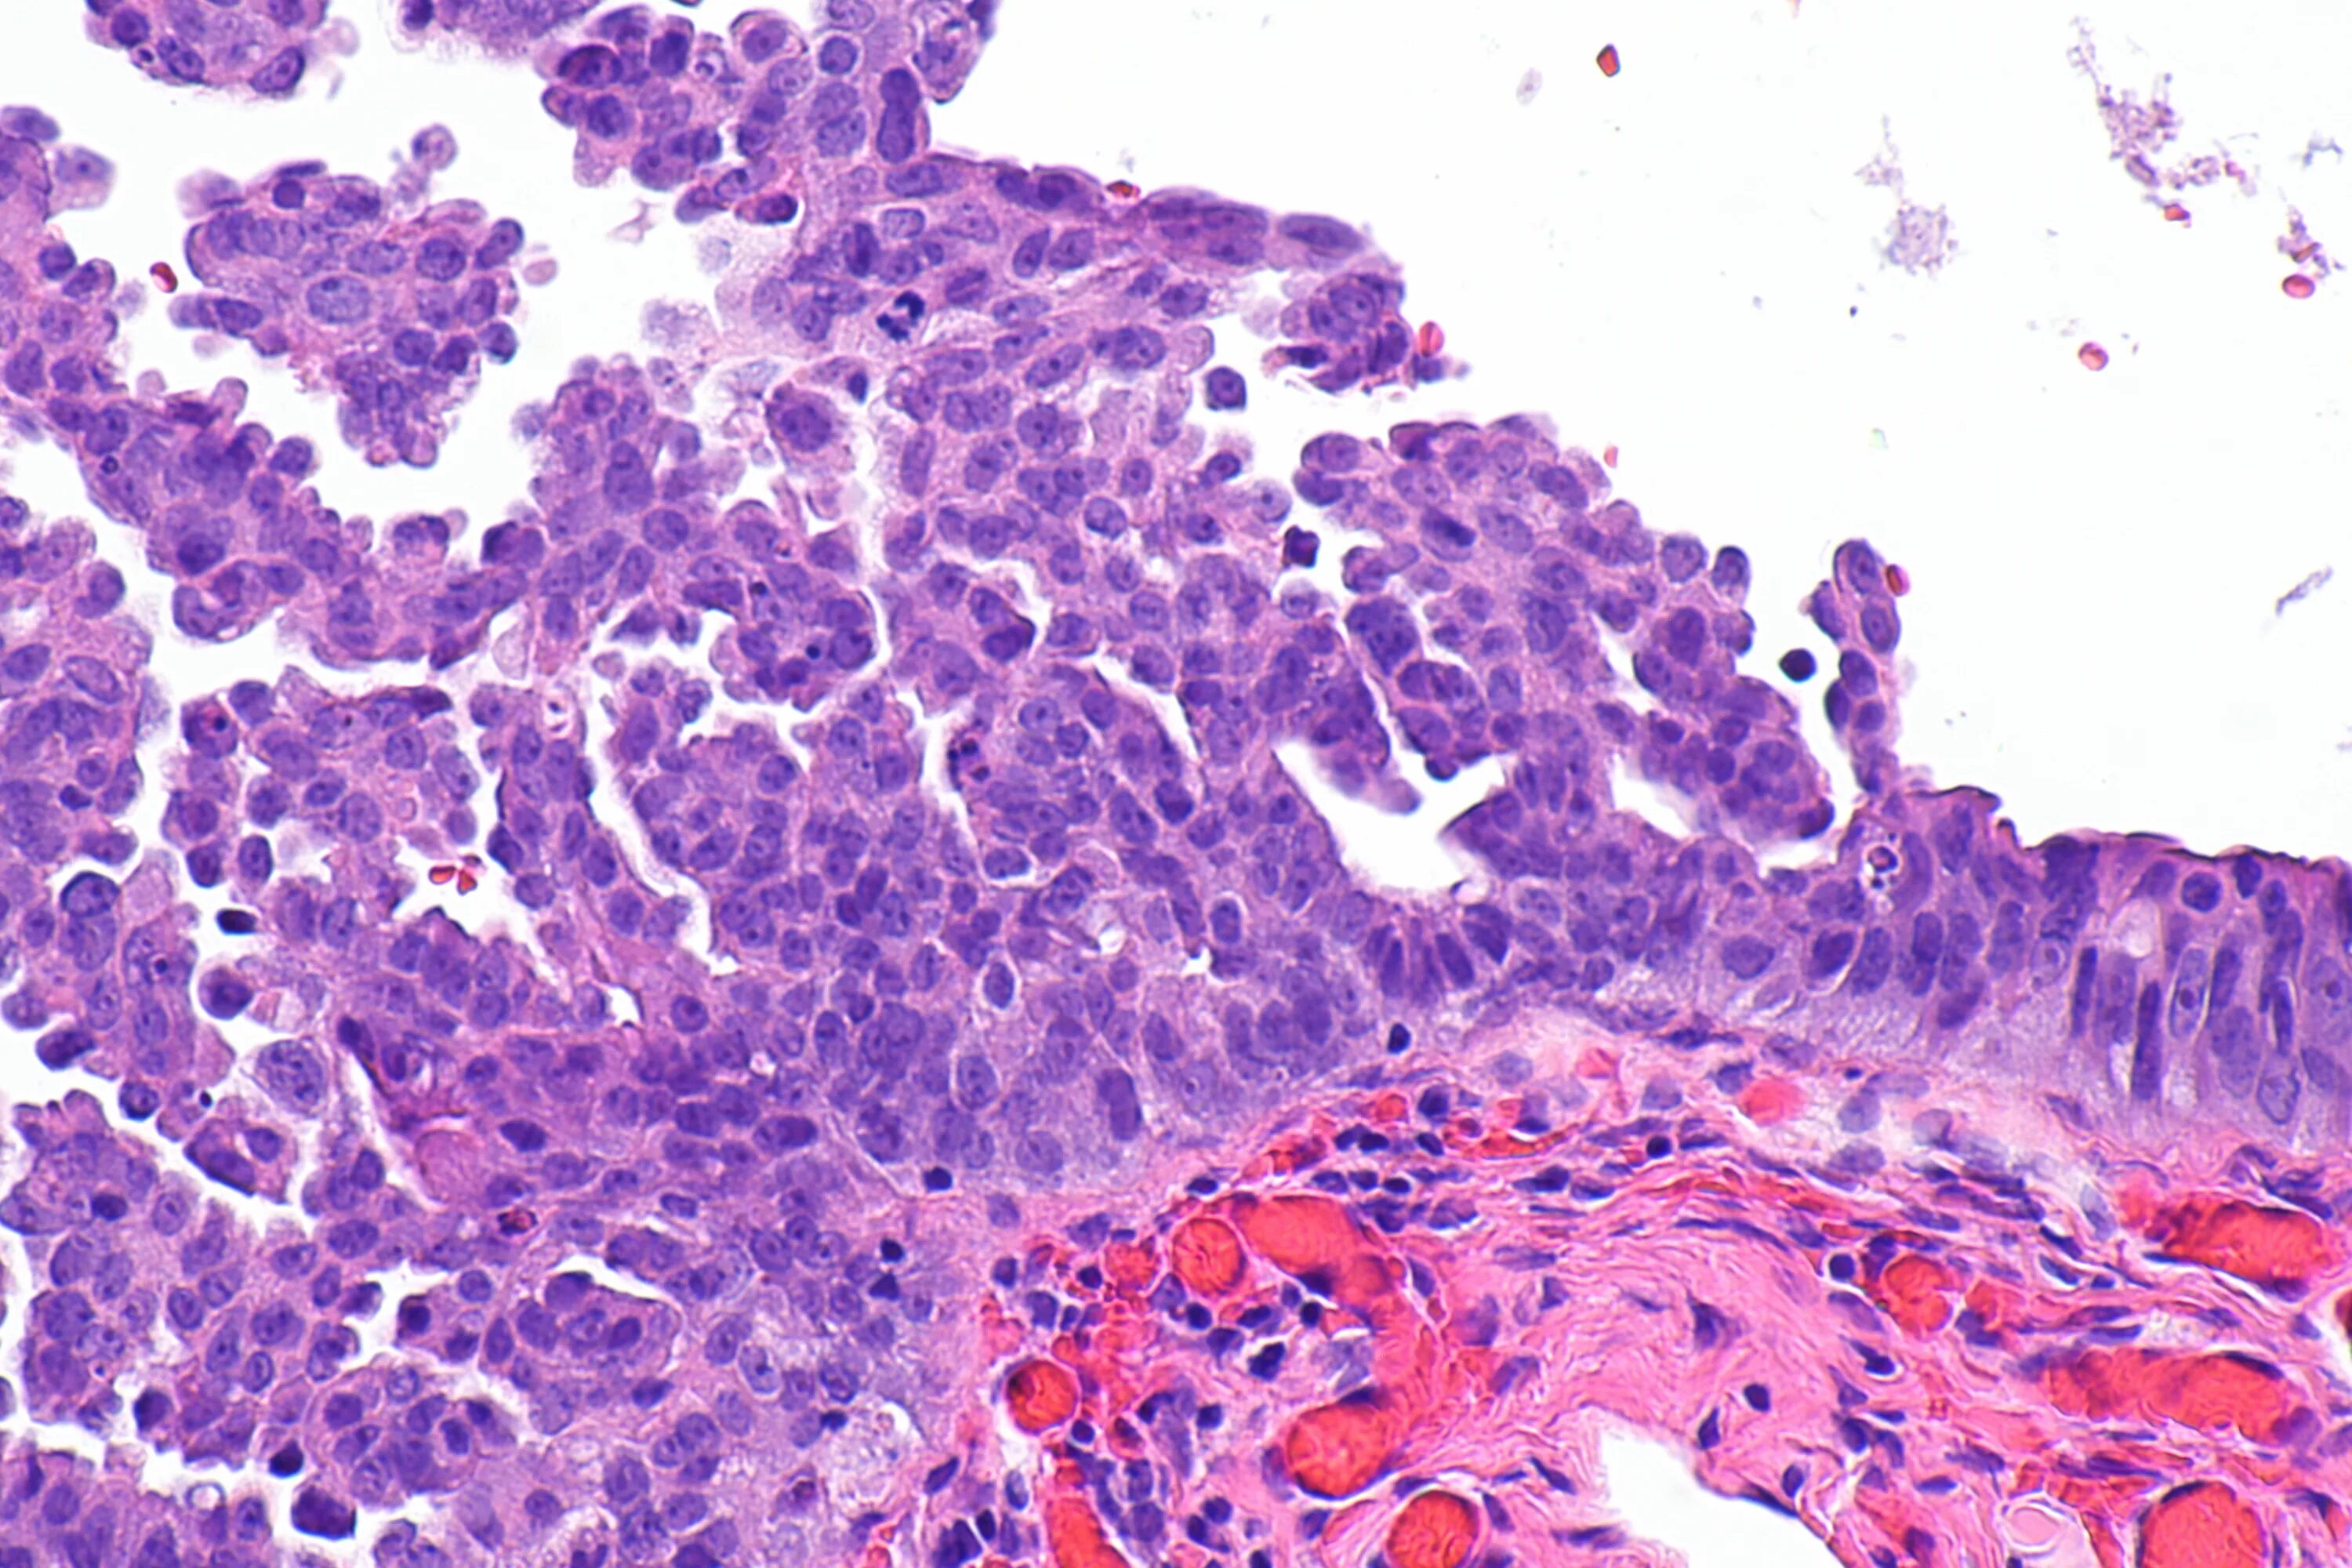

Гистологические варианты